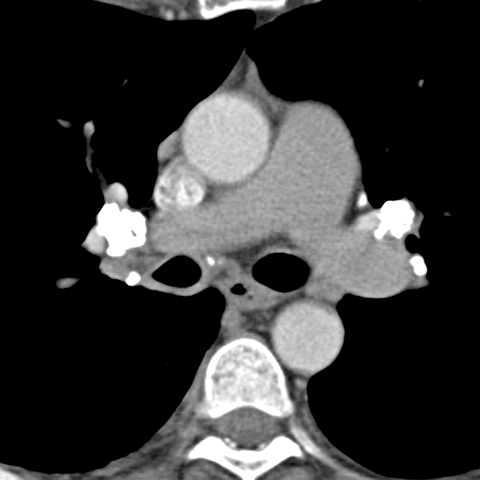

Calcified Hilar Nodes, Remote Granulomatous Infection [4 of 4]